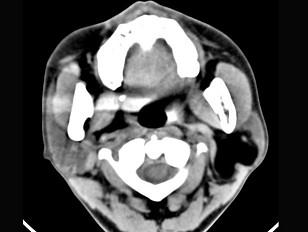

问题 男性38岁,左侧腮腺渐进性肿大一年,无压痛,CT扫描如图所示,请选择正确的描述和结论 ( )

选项 A、考虑为脂肪瘤 B、考虑为血管瘤 C、肿块边缘清楚,未见邻近结构受侵 D、考虑为囊肿 E、左侧腮腺区见低密度肿块,CT值约为-200Hu

答案 ACE